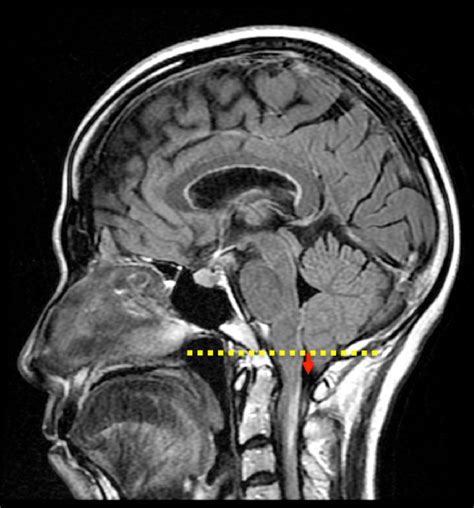

Finding out that you or a loved one has low lying cerebellar tonsils on an MRI report can be a source of significant anxiety. Often discovered incidentally during imaging for unrelated issues like headaches or neck pain, this finding frequently leaves patients wondering what it means for their long-term health. The cerebellar tonsils are the bottom-most parts of the cerebellum, the portion of the brain located at the base of the skull responsible for motor control and balance. When these structures extend below the foramen magnum—the large opening at the base of the skull where the spinal cord connects to the brain—it is referred to as having low lying cerebellar tonsils. While this can be a precursor to conditions like Chiari malformation, it is important to understand that not all instances require medical intervention.

To grasp the significance of low lying cerebellar tonsils, one must first understand the craniocervical junction. The skull provides a rigid, protective casing for the brain. Under normal circumstances, the cerebellum stays within the cranial cavity, resting just above the foramen magnum. When these tonsils descend, they can potentially crowd the spinal canal, impacting the flow of cerebrospinal fluid (CSF).

Diagnostic Processes and Imaging

The diagnosis of low lying cerebellar tonsils is almost exclusively made through magnetic resonance imaging (MRI). Because the brain and soft tissues are difficult to visualize on X-rays or CT scans, an MRI of the brain and cervical spine is the gold standard. A radiologist will measure the distance the tonsils extend below the foramen magnum. Typically, a descent of 5 millimeters or more is often used as a clinical threshold for potential Chiari malformation, though this is not a hard-and-fast rule.